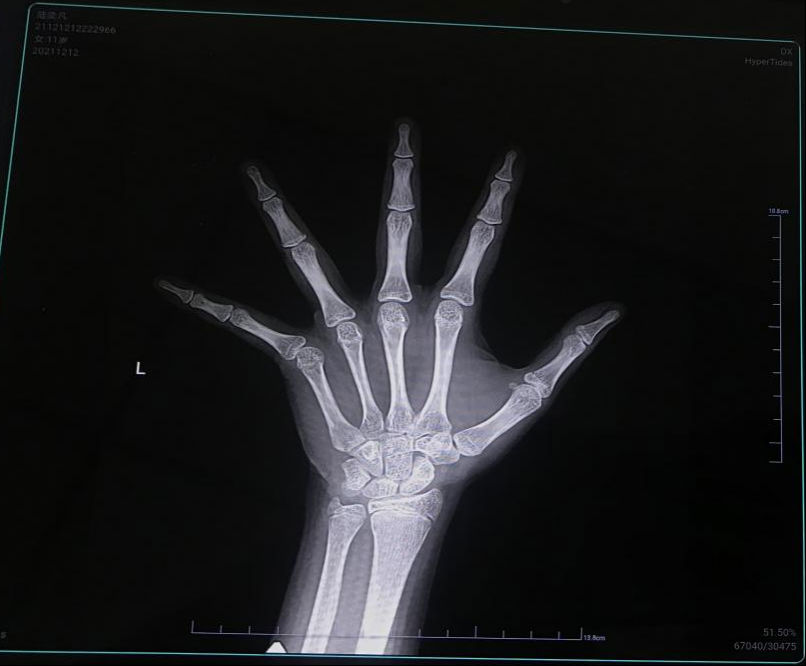

12月12日,福建醫科大學附屬第一醫院門診樓8層兒童生長發育??崎T診,坐滿了前來參加義診活動的家長和孩子。當天,我院兒科專家為200多名3-15歲兒童免費測骨齡、提供相關資訊、評估生長發育情況,受到了許多家庭的點贊。而在這200多名孩子當中,竟然有30多個孩子骨齡異常。

現場全天坐診的我院兒科洪琳亮副主任醫師表示,由當日活動情況來看,不少家長朋友們仍對骨齡的認知存在嚴重的認知不足,不知道骨齡在兒童生長發育期間的意義。還有多位家長因為疏于孩子的身高管理,拍完骨齡后才發現小朋友的骨骺已經提前閉合,身高最終只能停留在較矮甚至矮小的水平。

判斷孩子還能不能長、能長多少,要看孩子的骨齡狀況。通過拍攝孩子左手腕部分的X光片,能看到孩子生長空間、潛力有多少。 孩子骨骺一旦閉合,孩子就很難增高了!

骨齡差在±1歲內~正常

骨齡>年齡1歲,不超過2歲~偏早

骨齡<年齡1歲,不超過2歲~偏晚骨齡<年齡2歲以上~異常落后

骨齡>年齡2歲以上~異常提前